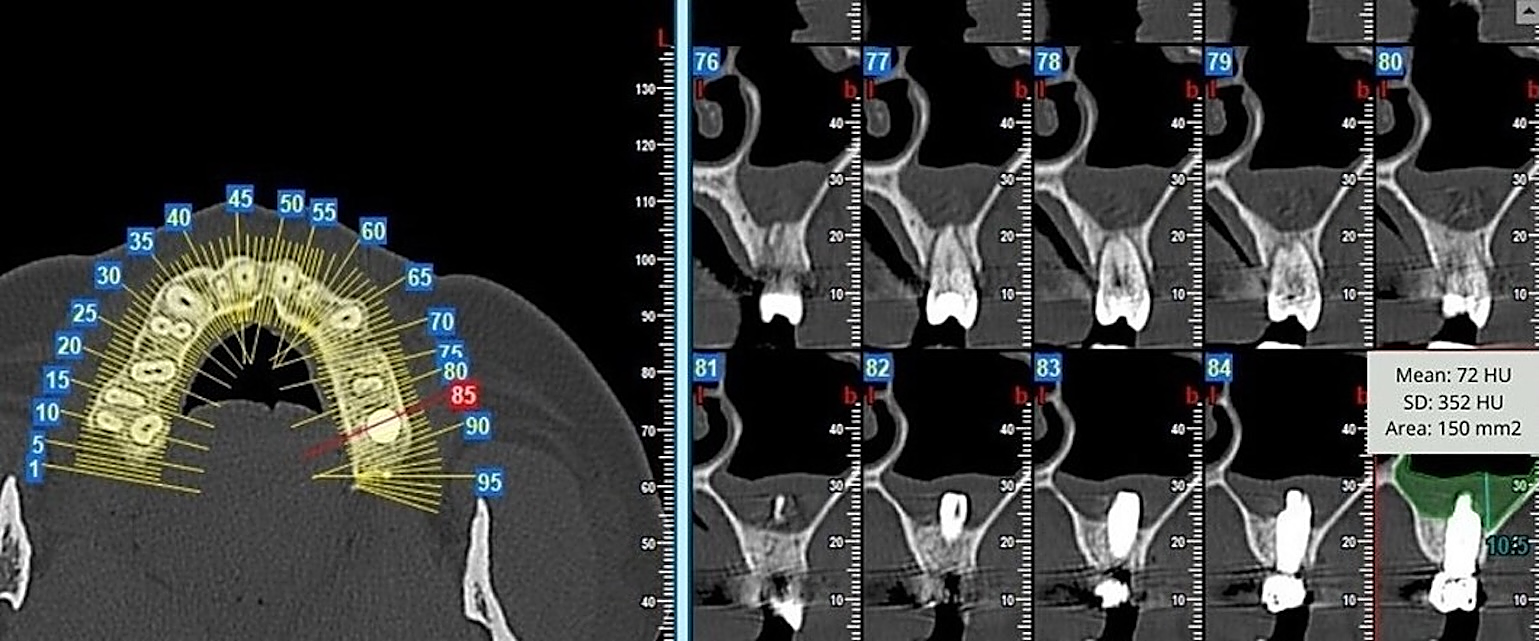

2.5. Morphometric Measurements

| Patient | SMT Pattern | SMT Area (mm2) | SMT Density (HU) | SMT Max Height (mm) T1-T0 | |||||

|---|---|---|---|---|---|---|---|---|---|

| Pn | Ort | Ax | Pn | Ort | Ax | Pn | Ort | ||

| 1 | C | 221.94 | 153.36 | 280.98 | 242.4 | 63.4 | 287.1 | 17.1 | 16.7 |

| 2 | C | 160.9 | 118.26 | 141.03 | 74.2 | 306.8 | 461.3 | 11.9 | 13.1 |

| 3 | C | 117.45 | 57.15 | 172.8 | 261.8 | 353.9 | 558.6 | 3.1 | 2.1 |

| 4 | H | 201.33 | 50.4 | 191.43 | 119.2 | 343.3 | 205.1 | 11.2 | 2.7 |

| 5 | C | 348.39 | 119.07 | 209.61 | 165.3 | 81.2 | 307.5 | 19.2 | 11.7 |

| 6 | H | 321.66 | 129.42 | 236.52 | 86.1 | 35.8 | 247.1 | 11.4 | 9.2 |

| 7 | H | 114.12 | 70.74 | 111.78 | 152.2 | 430.8 | 256.3 | 17.7 | 6.0 |

| 8 | C | 289.35 | 207.9 | 364.32 | 196.5 | 107.7 | 165.0 | 19.7 | 19.5 |

| 9 | C | 506.34 | 153.09 | 310.14 | 166.3 | 113.2 | 197.4 | 18.0 | 14.9 |

| 10 | C | 116.73 | 72.75 | 109.53 | 145.0 | 108.3 | 365.9 | 15.9 | 2.3 |

| 11 | C | 411.12 | 209.88 | 317.16 | 128.0 | 91.4 | 219.4 | 21.3 | 23.6 |

| 12 | C | 169.11 | 96.39 | 99.36 | 23.7 | 179.5 | 480.0 | 16.7 | 3.6 |

| 13 | C | 112.32 | 58.95 | 82.26 | 96.1 | 41.8 | 247.3 | 2.4 | 3.0 |

| 14 | H | 199.89 | 111.33 | 404.37 | 21.8 | 186.6 | 343.3 | 9.9 | 13.2 |

| 15 | C | 234.54 | 85.5 | 269.73 | 71.2 | 428.5 | 178.8 | 9.3 | 9.8 |

| 16 | C | 78.84 | 17.55 | 60.12 | 366.2 | 404.8 | 271.0 | 4.2 | 2.8 |

| 17 | C | 219.24 | 105.39 | 189.63 | 179.9 | 703.4 | 327.3 | 8.1 | 4.5 |

| 18 | C | 173.52 | 97.74 | 233.73 | 248.2 | 188.7 | 320.5 | 5.1 | 12.4 |

| 19 | H | 136.26 | 36.63 | 120.87 | 72.5 | 218.4 | 584.0 | 3.0 | 3.2 |

| 20 | C | 223.74 | 154.71 | 290.88 | 335.7 | 115.5 | 395.6 | 3.7 | 10.5 |

| 21 | H | 238.32 | 83.97 | 89.73 | 295.1 | 278.1 | 582.0 | 4.5 | 3.4 |